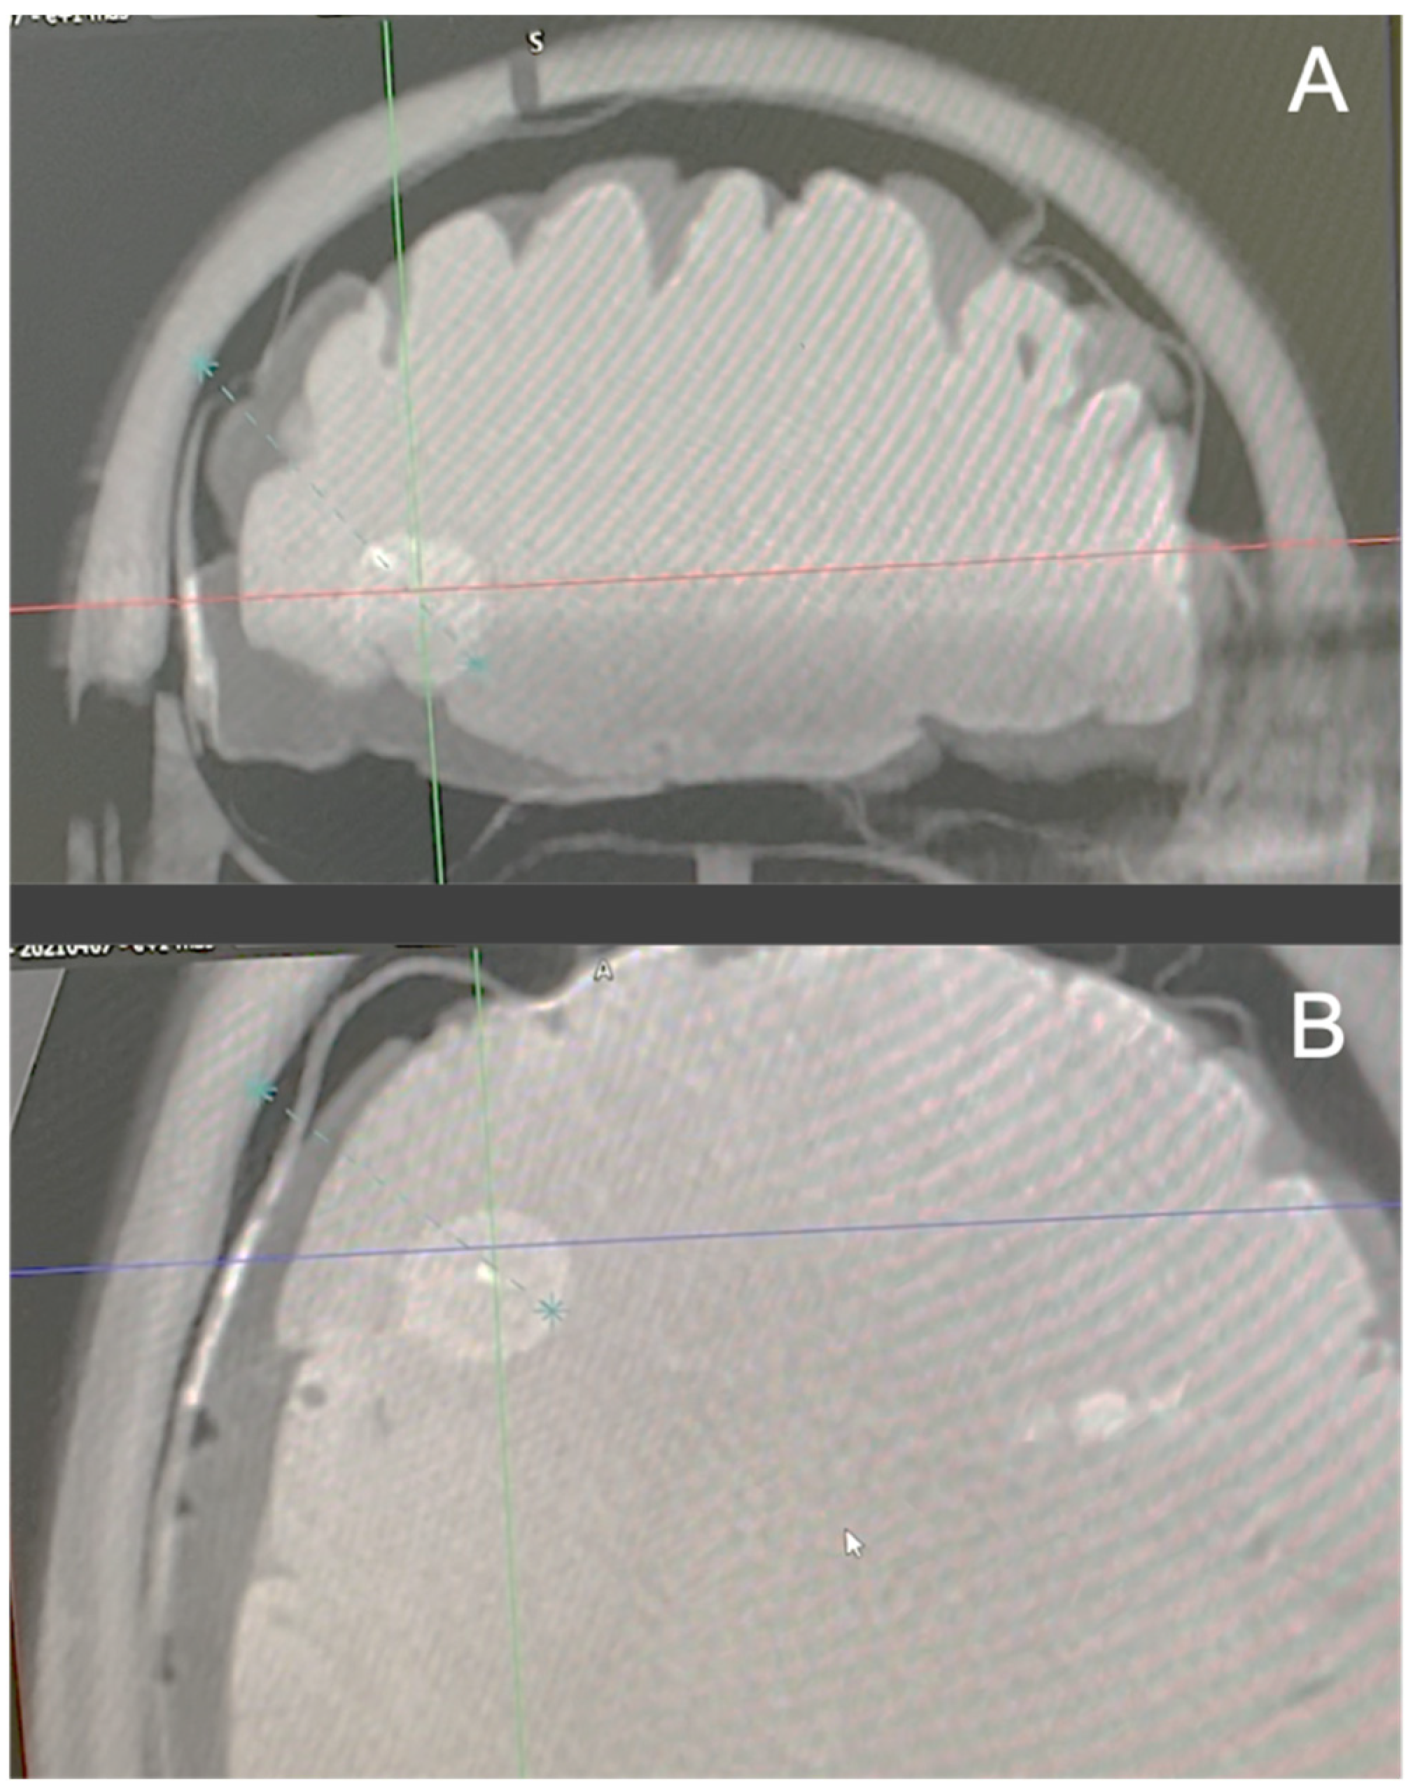

2.1.1. Brain Imaging

2.2. Surgical Procedure